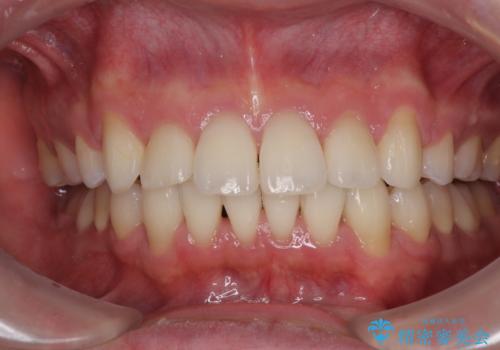

上顎のみの抜歯矯正であったため、治療期間が長期化することが予想されましたが、何とか3年弱の期間で想定通りの仕上がりで終えることができました。